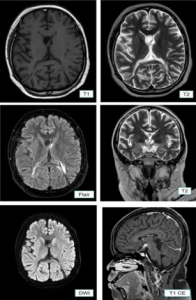

FK-KMK UGM. Dosen Fakultas Kedokteran, Kesehatan Masyarakat, dan Keperawatan (FK-KMK) UGM memublikasikan artikiel ilmiah dengan judul “Alterations of Klotho Protein Expression in the Kidney of